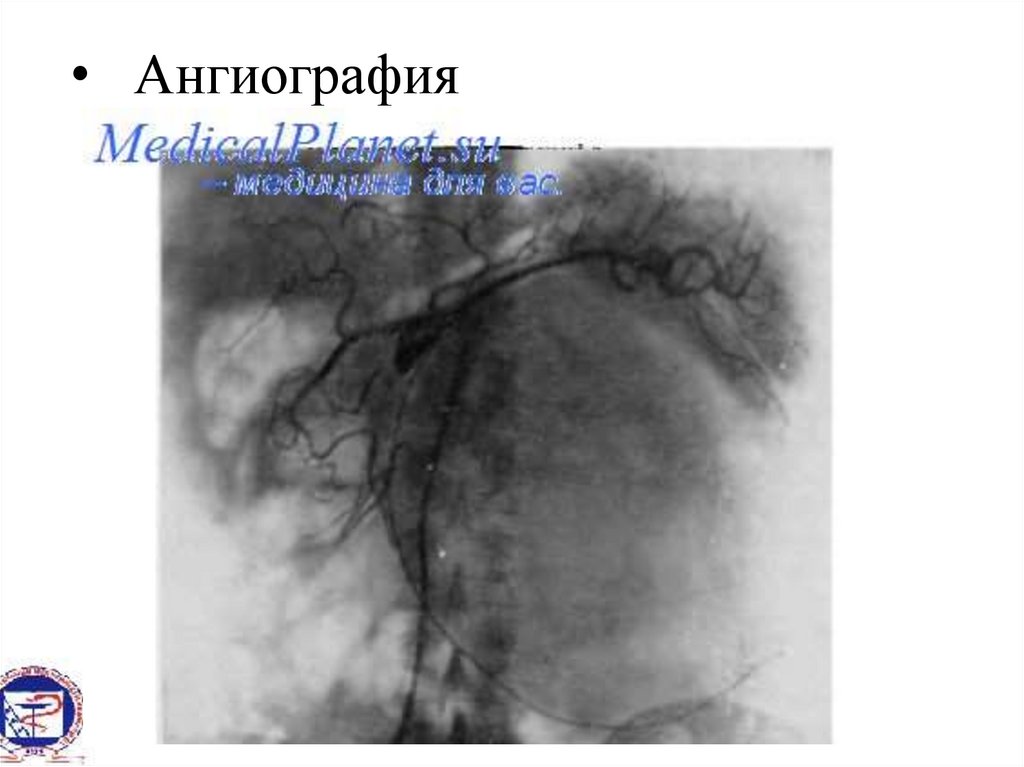

• Ангиография